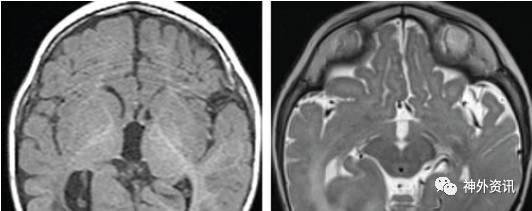

出现残留的癫痫发作的患者需要再次接受高场强的MRI和DTI检查,来评估半球间神经传导离断的程度。由于脑室内操作的空间限制,半侧巨脑症患者有很大可能性出现不彻底的离断术。

脑积水

尽管接受了环岛叶半球离断术的患者脑积水发生的可能性要低于接受半球切除术的患者,但是仍然在术后有2%-15%左右的发生率。当患者表现为半侧巨脑症或者多发皮层发育不良时,产生脑积水并且需要在术后接受永久的脑室腹腔分流术的几率明显增高。